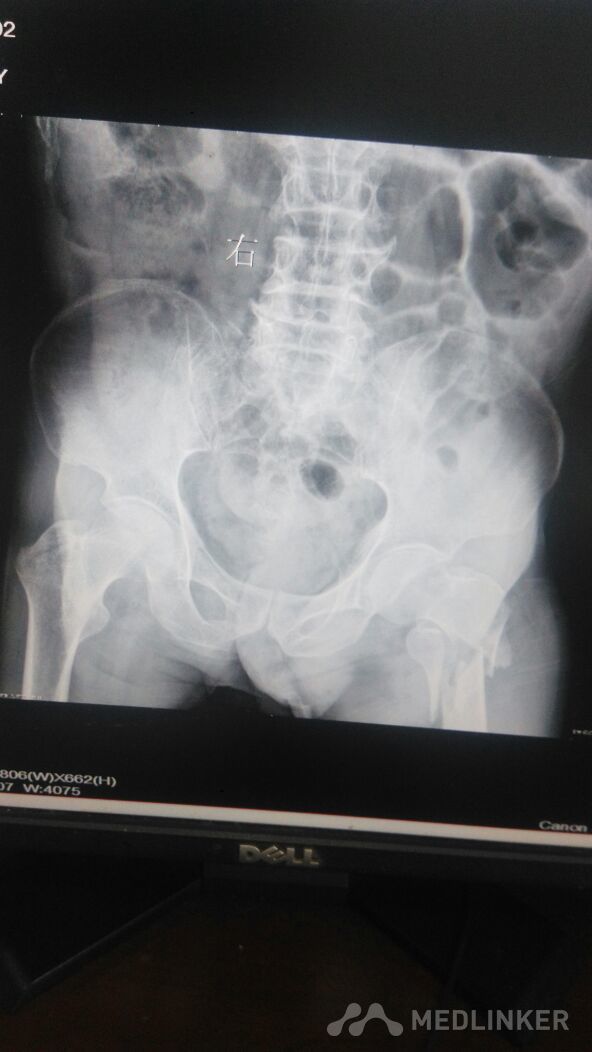

左侧股骨转子间骨折,右侧股骨大转子骨折。

高龄老人,94岁。外伤摔倒致髋部肿痛,左,右,髋部均压痛阳性,叩痛阳性。双髋关节活动受限。

走路时摔倒致左髋部肿痛1小时,左髋部肿胀明显,压痛,阳性,叩痛,左足血运正常。

左股骨转子间骨折,右侧股骨大转子骨折。手术治疗。

内科疾病较多。保守治疗希望不大。家属有所顾虑。不知道有好的办法吗?